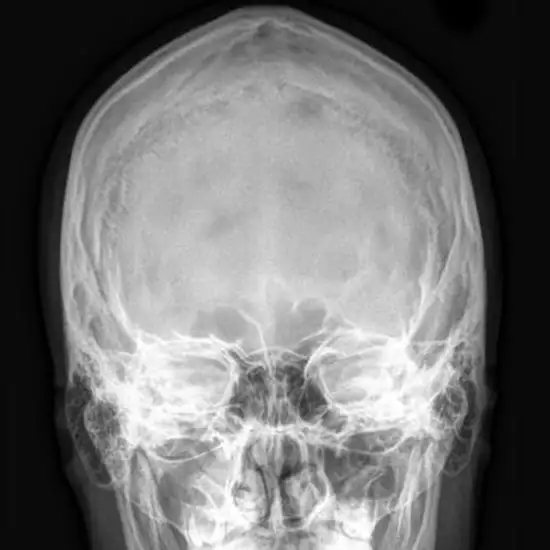

What is an X-ray Mandible AP/Oblique Views Test?

An X-ray of the mandible (jaw) is used to see the structures of the jaw bone, the temporomandibular joint (TM joint), and the soft tissues like muscles around them.